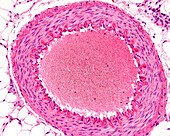

13633589 - Arteriole, light micrograph